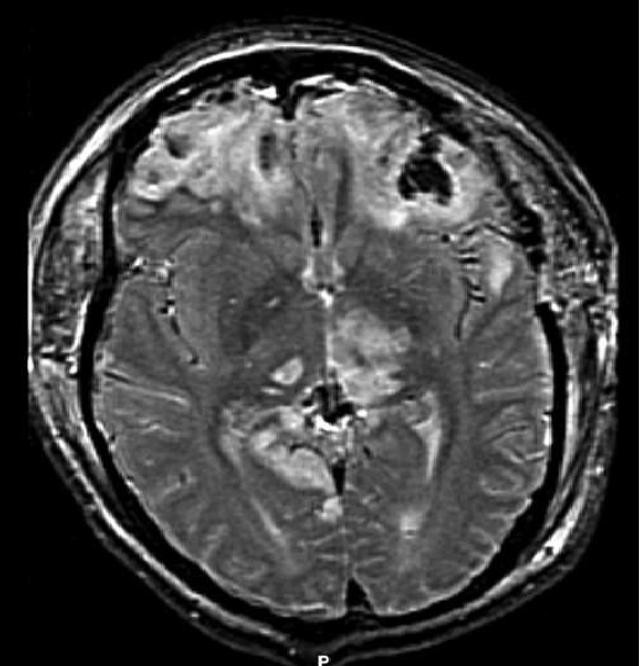

Subdural Hematoma

An accumulation of blood on the surface of the brain is known as a subdural hematoma.

Subdural hematomas develop after trauma because the bridging veins between the dura and arachnoid rupture.

Radiology of subdural hematomas reveal a lesion with a crescent shape.

Subdural hematomas may present with neurologic symptoms that progress with the severity of the hematoma.

Age-related cerebral atrophy, which stretches the veins, contributes to an increased incidence rate of subdural hematomas in the elderly.

Herniation is a potentially lethal complication of a subdural hematoma.